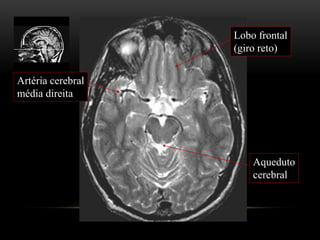

ANATOMIA TOPOGRÁFICA

Plano axial

Artéria cerebral

média direita

Lobo frontal

(giro reto)

Aqueduto

cerebral